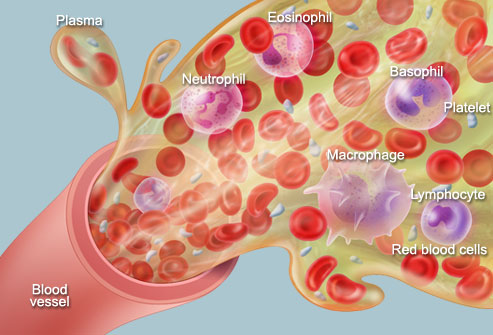

- Components of blood and their functions (Red blood cell, white blood cell, platelets and plasma (blood groups)

- Blood vessels (arteries, veins, and capillaries)